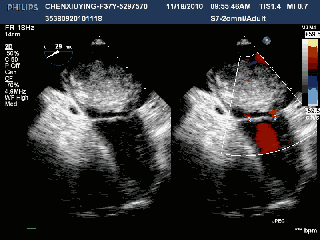

图 2 cw 示动脉导管未闭分流频谱,呈连续性,占据整个心动周期 肺动脉